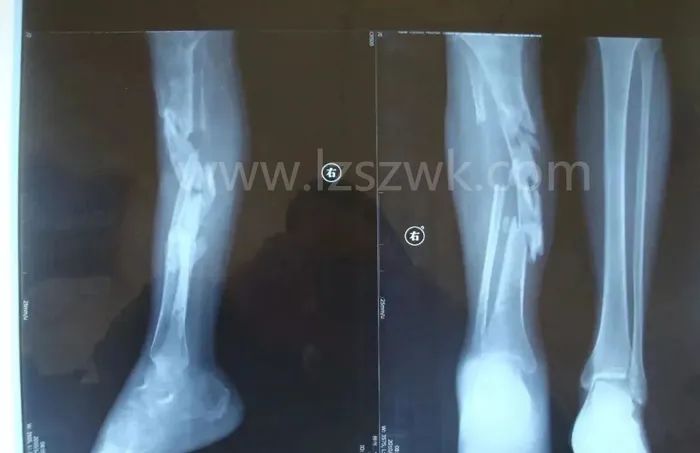

在大段骨缺损治疗过程中,促进骨愈合的首要条件是稳定骨折断端,既往常使用钢板固定骨折断端,但钢板固定剥离软组织及骨膜范围广泛,对骨缺损部位的血运破坏更大,且易造成植骨段螺钉松动和钢板断裂。交锁髓内钉联合骨移植技术目前已广泛应用于骨缺损的临床治疗上,该技术选择交锁髓内钉这一“生物性内固定”方式,维持骨缺损部位的稳定性,并将植骨材料填充于缺损处,进一步加强了骨折断端之间的稳定性,保留了骨传导性,同时对新生骨痂有诱导成骨作用,加快了骨缺损修复速度,提高愈合率,有文献报道曾使用交锁髓内钉联合骨移植修复长达15cm骨缺损。